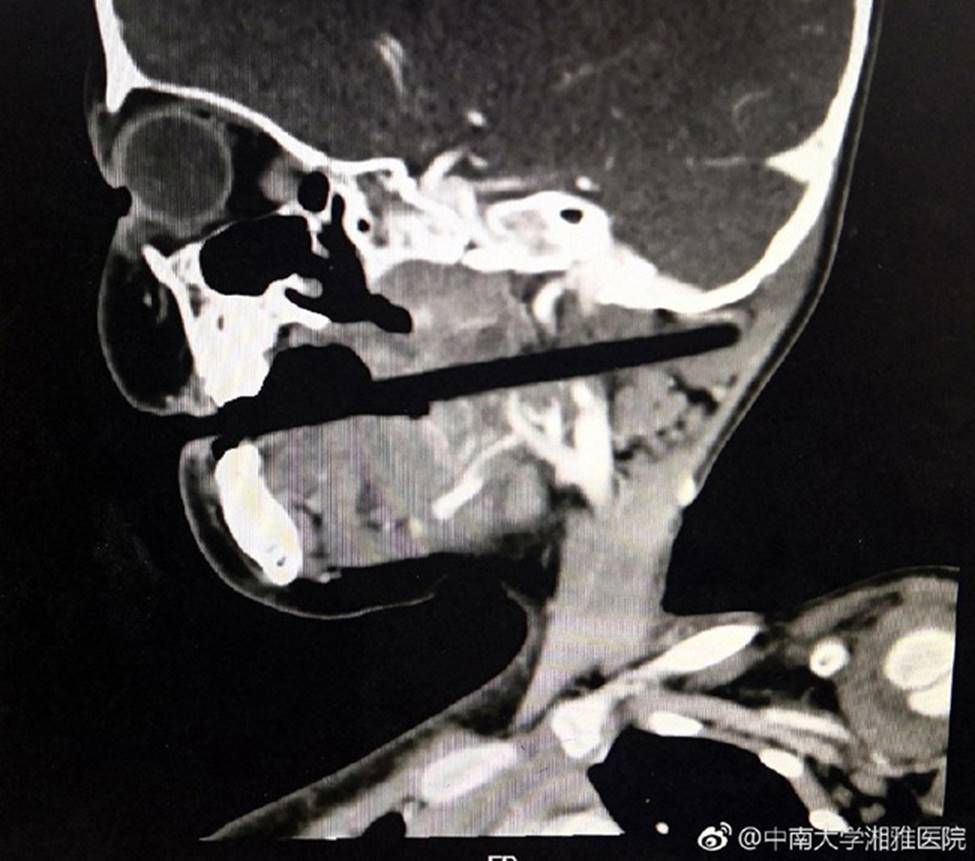

Cận cảnh chiếc đũa đâm thẳng vào hộp sọ của bé gái

Kết quả chụp CT cho thấy chiếc đũa đã bị trượt hẹp trong các phần quan trọng như thân não, động mạch cảnh và đốt sống cổ. Tuy nhiên, khoảng 10cm của chiếc đũa đã bị đâm vào đầu của đứa trẻ, vì vậy các bác sĩ đã quyết định thực hiện phẫu thuật mặc dù có những rủi ro liên quan đến việc gây mê.

Bức ảnh chụp X-quang cho thấy mức độ đáng sợ của tai nạn